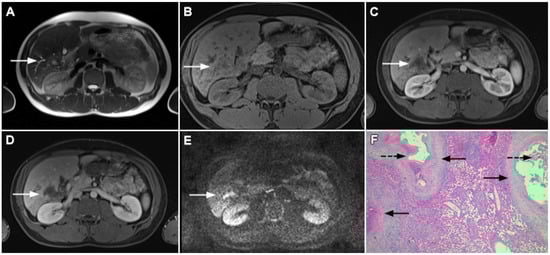

Figure 1.

Typical intrahepatic mass-forming cholangiocarcinoma in 68-year-old woman. On axial T2-weighted image a lobular heterogeneously hyperintense tumor (arrow) is seen, located centrally in the liver segment IVB (A). The lesion (arrow) is hypointense in a plain T1-weighted image (B) with irregular ring enhancements in the arterial phase (C) and progressive enhancement in the portalvenous (D) and delayed phase (E). Note the perilesional biliary dilatation. Hematoxylin and eosin (H&E) staining (F) showed cholangiocarcinoma (arrow) and normal liver parenchyma next to the tumor (dashed arrow); original magnification ×40.

However, in highly fibrotic lesions or in lesions with internal necrosis, central parts may remain non-opacified even on delayed images (Figure 2) [14].

Figure 2.

Mass-forming intrahepatic cholangiocarcinoma in 72-year-old man. Irregular heterogeneously hyperintense lesion (arrow) on T2-weighted image (A) located in liver segments IVB and III with peripheral biliary dilatation is shown. On a plain T1-weighted image (B) the lesion (arrow) is hypointense with only discrete ring enhancement in the arterial phase (C) but without detectable enhancements in the portal venous (D) and delayed phases (E). Hematoxylin and eosin (H&E) staining (F) showed poorly differentiated cholangiocarcinoma (dashed arrow); normal liver parenchyma is also shown (arrow); original magnification ×40.